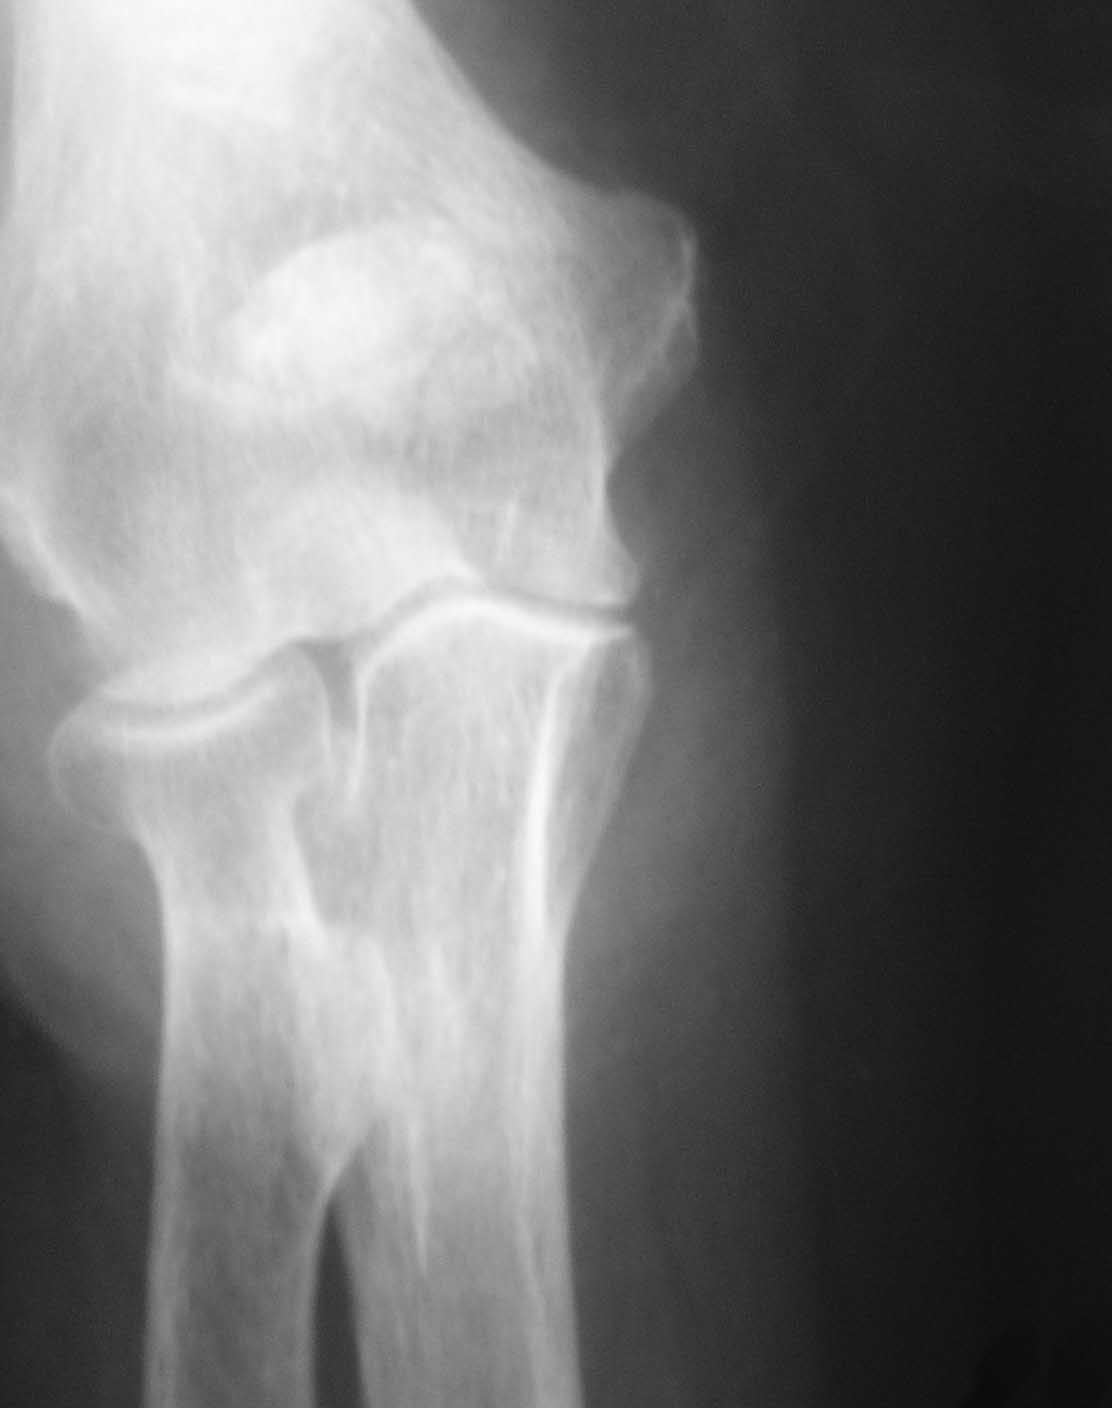

Обстоятельства дела. Пациентка Ш., 85 лет, поступила в отделение с

оскольчатым переломом локтевого отростка с диастазом отломков. Из

сопутствующей патологии: гипертоническая болезнь III ст.Б,  АГ III ст,

сахарный диабет, варикозное расширение вен н/конечностей, костный

анкилоз левого локтевого сустава в порочном положении (после травмы

более 30 лет назад). При более  детальном осмотре рентгенограмм выявлен

многооскольчатый перелом локтевого отростка с диастазом отломков,

остеопороз (см. фото 1,2).

1) перелом - не оскольчатый, а раздробленный, с  повреждением большей

части локтевого отростка (С2 по А0, Тип  IIIB по Mayo) с явлениями

остеопороза, сминания промежуточных костных фрагментов.  Подтверждением

этому является наличие промежуточных костных фрагментов неопределенной

формы, несоответствующей суставной части локтевого отростка, а также

хорошо видимый передний подвывих  костей предплечья (см. фото 2).